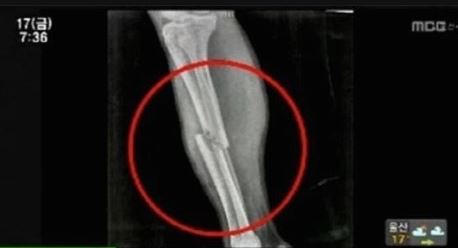

뼈의 강도가 약해지면서 쉽게 골절되는 골격계 질환입니다. 뼈의 강도는 뼈의 양과 뼈의 질에의해서 결정됩니다. 뼈의 질에 영향을 주는 요소로는 뼈의 구조,교체율,무기질화,미세 손상등이 있습니다.

골다공증의 진단은 병원의 BMD장비로(즉 X-RAYY)진단하며 허리와 대퇴골등의 골밀도를 측정하여 골다공증을 진단합니다. 가격은 1만원 이하로 측정되고 있습니다.